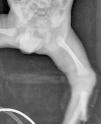

Recién nacido de 32 semanas de edad gestacional y 1.320 g de peso que ingresa en UCIN por prematuridad. Corresponde a la primera gestación controlada en madre sana. Serologías maternas negativas. En las ecografías prenatales se evidencia embarazo gemelar monocorial biamniótico sin malformaciones. Amniocentesis realizada: cariotipo XY en ambos fetos. Frotis vaginal y rectal desconocidos para Streptococcus agalactiae. Cesárea urgente a las 32 semanas por Doppler patológico del segundo gemelo y pérdidas hemáticas maternas. Amniorrexis intracesárea. Nace el primer gemelo con peso al nacimiento de 1.320 g, longitud de 40,5 cm, PC de 27 cm, Apgar 7/9 y pH de arteria umbilical 7,35. Desde sala de reanimación precisa ventilación con presión positiva continua en vía aérea (CPAP) por lo que se traslada a la UCIN. Allí se inserta un catéter sylastic central percutáneo en el miembro inferior izquierdo para iniciar la nutrición parenteral. Recibe soporte ventilatorio con CPAP (fracción inspiratoria de oxígeno [FiO2] máxima 0,30; presión máxima 7 cmH2O) y tratamiento con cafeína por apneas asociadas a la prematuridad. Se inicia antibioterapia con ampicilina y gentamicina por riesgo de infección (estado de portador materno a S. agalactiae desconocido). Al quinto día de vida se evidencia tumefacción en genitales externos con edema importante del saco escrotal (fig. 1). Se orienta inicialmente como hidrocele y se decide una actitud expectante. A las 24 h se constata una progresión de la hinchazón escrotal y edema del pene sin afectación de las extremidades inferiores ni acumulación de líquido en otras localizaciones. El saco escrotal es blando a la palpación y no parece doloroso, la transiluminación demuestra líquido en su interior y en la piel escrotal se observa una pequeña herida con mínima solución de continuidad y bordes eritematosos. Inicialmente se orienta el cuadro como una sospecha clínica de infección con puerta de entrada cutánea. Se extrae hemocultivo y se inicia antibioterapia empírica con teicoplanina y ceftazidima. La analítica no evidencia alteración en los parámetros de infección. Revisando la radiografía realizada para control del sylastic central percutáneo se observa que el trayecto de éste llega tortuosamente hasta la zona escrotal (fig. 2). Dada la sospecha de introducción del catéter hasta los vasos espermáticos a través de la vena ilíaca con obstrucción del flujo venoso y posterior acumulación de líquido, se decide retirar el catéter sylastic. A las 12 h de la retirada del mismo desaparece la tumefacción escrotal y el pene vuelve a tener un aspecto totalmente normal. El resultado del hemocultivo es negativo por lo cual se suspende la antibioterapia a los 3 días. Evolución posterior sin incidencias.

Figura 1. Tumefacción escrotal del paciente.